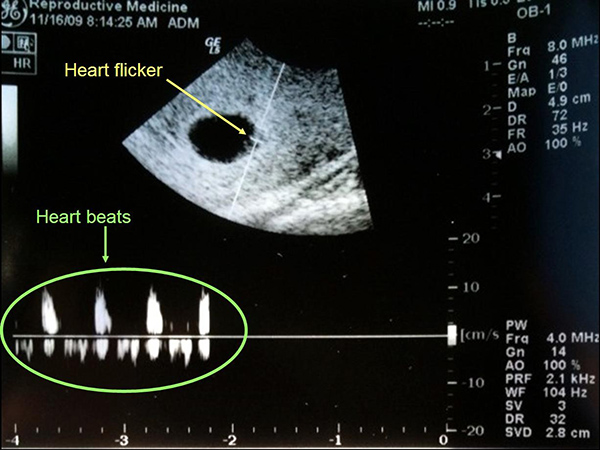

Theo thể trạng của mẹ và tốc độ phát triển của bé cũng khác nhau. Thông thường, khoảng từ tuần thứ 7 là mẹ đã có thể nghe thấy nhịp tim của bé thông qua siêu âm. Cũng có nhiều trường hợp tim thai đã xuất hiện ở tuần thứ 5, thứ 6 của thai kỳ, thậm chí là đến tuần thứ 10 mới có thể nghe thấy nhịp đập của bé.

Đến tuần thứ 12 của thai kỳ, tim bé được xem như đã hoàn thiện và cs thể thực hiện chức năng của nó là vận chuyển máu. Đến tuần thứ 14, nhịp đập của bé sẽ mạnh mẽ và rõ ràng hơn. Sang đến tuần thứ 16, mỗi ngày tim bé có thể bơm lượng máu lên đến 14 lít.

Đến những tuần tiếp theo, tim bé sẽ càng phát triển về kích thước lẫn khối lượng. Thông thường nhịp đập của bé vào khoảng 120 – 160 lần / phút, vào những lúc vận động nhiều có thể lên tới 180 lần / phút lớn gấp đôi nhịp đập của người bình thường.